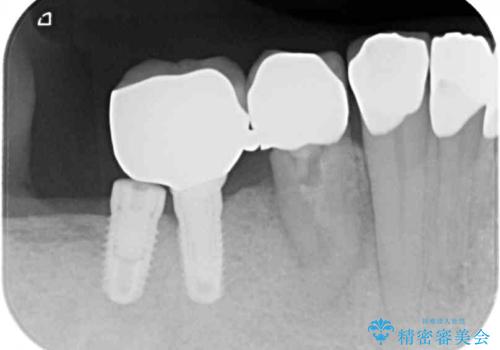

以前にも歯が割れてインプラント治療を行いましたが、抜歯してからインプラント埋入→仮歯装着までに半年以上を要し、その間に残された歯への負担が大きくなり、左右反対側のセラミッククラウンが破折したことがありました。

そのため、当院に新しく導入した手法により、抜歯をした日にインプラントを埋入し、そのままを仮歯を装着することで、他の歯への負担を軽減する計画を立てました。

インプラント埋入時に植立具合の安定性を測定したところ、十分な数値が得られたため、速やかに仮歯を装着して咬合回復をさせることができました。